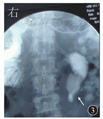

患者男,56岁,因"反复腹胀伴恶心、呕吐6个月"于2018年6月18日入住哈尔滨医科大学附属第一医院。患者6个月前无明显诱因出现腹部胀痛,以脐周为主,无放射痛,伴恶心、呕吐,呕吐物为黄绿色水样物,同时肛门排气减少。对症治疗后症状好转。2018年5月患者再次出现上述症状,发作时排气减少,呕吐胃内容物后症状可缓解。自行购买益生菌、中药服用半个月后自觉好转。2018年6月11日患者出现相同症状,恶心、呕吐较前加重,呕吐物为食物伴有胆汁。6月14日于当地医院行胃肠镜检查,诊断为胆汁反流性胃炎,给予相应治疗后未见好转,腹胀加重,排气、排便消失。6月18日急诊入住哈尔滨医科大学附属第一医院,考虑肠梗阻,入院时体格检查示无欲貌,意识不清,慢性病容,血压为98/62 mmHg(1 mmHg=0.133 kPa),心率为100次/min,腹部饱满,腹部叩诊呈鼓音。给予胃肠减压、禁食水、补液、营养支持治疗。6月23日患者视物重影,目光呆滞;25日出现嗜睡症状,病情进行性加重;27日因晕厥转入重症监护病房,给予气管插管、抗炎、对症支持治疗。2018年7月5日行头颅MRI检查,确诊韦尼克(Wernicke)脑病;7月9日行腹部CT检查见右侧肠管扩张、积气、积液,左中下腹局部肠系膜旋转(图1)。腹部计算机断层扫描血管造影(computed tomography angiography, CTA)检查见肠系膜上动脉及其分支移位、旋转(图2)。神经内科和普外科会诊后建议经口置入肠梗阻导管,经肠梗阻导管注入少量流食,口服肠道益生菌,辅以胃肠黏膜保护剂,补充维生素B1、B6,纠正电解质紊乱,以及充分静脉营养支持等治疗。2018年8月10日患者腹胀减轻,无恶心、呕吐,有自主排气、排便,意识好转,给予经口半流质饮食;半流质饮食6 d后患者腹胀加重,伴恶心、呕吐,呕吐物为胆汁,排气、排便消失。回顾病史,患者住院期间反复多次出现禁食数日后症状减轻,半流质饮食数日后症状加重。2018年8月16日行直立位上消化道造影检查示近段空肠扩张,呈螺旋状,可见液气平面,动态观察可见肠管逆蠕动(图3)。小肠镜检查可见距幽门40 cm处小肠走行扭曲,呈"S"形,其口端肠腔明显扩张、绒毛结构变平、环形皱襞消失(图4)。患者于2018年9月24日行腹腔镜下小肠切除吻合术治疗,术中见近段小肠和肠系膜血管顺时针旋转(图5),远端梗阻扩张空肠位于肠管穿入肠系膜处,由对侧小肠系膜穿出,延续至回盲部,术中诊断为中肠旋转不良。2018年11月20日患者恢复良好而出院。

影像学检查对中肠旋转不良的诊断至关重要。多普勒超声检查对诊断中肠旋转不良具有一定价值,扩张的肠管和肠系膜上静脉以顺时针方向缠绕肠系膜上动脉,扭曲的肠系膜血管构成了漩涡符号,这是典型的旋转不良,甚至肠系膜上静脉反转至肠系膜上动脉的左侧,多普勒超声检查可以清晰地显示该现象[1,5]。腹部CTA成像同样可以清楚地显示肠系膜血管旋转情况,如本病例所示。腹部CT检查显示的漩涡征即螺旋状的肠系膜血管,这种体征并不是特异性的,也可能会在脾脏扭转等其他病理情况下出现。但腹部CT检查可以显示空肠扩张、积气、积液,提示梗阻和显示梗阻部位。据报道,上消化道造影检查判断中肠扭转的准确度为100%[6]。X线动态观察造影剂的通过情况可发现空肠蠕动异常,进而判断空肠梗阻的位置。本病例中,造影剂到达扩张的空肠时明显被稀释,说明空肠梗阻上方有积液,同时该位置的肠管出现逆蠕动现象,这样可以基本明确空肠异常旋转的存在和梗阻的位置。小肠镜检查的优势是可以在直视下进一步判断梗阻是器质性病变还是异常旋转,为手术提供直接证据,本病例经口小肠镜检查可见近段空肠走行扭曲。因此,上消化道造影和小肠镜检查在中肠旋转不良的诊断中具有非常重要的价值。